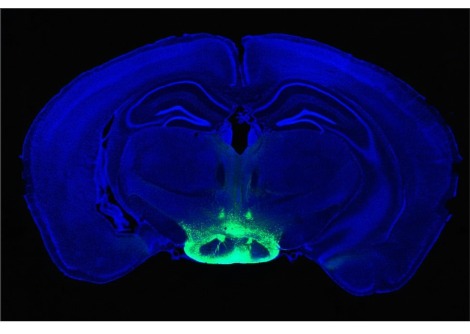

وللحصول على رؤية أكثر شمولاً، حلل أوري ألون وزملاؤه عينات دم جُمعت سابقًا من أكثر من 160 ألف امرأة ، تتراوح أعمارهن بين 25 و31 عامًا، واللواتي حملن مجتمعات بأكثر من 300 ألف حالة حمل. وقد وفرت هذه العينات مجتمعة لمحة عامة عن الجسم كل أسبوع من 20 أسبوعًا قبل الحمل إلى 18 شهرًا بعد الولادة، حيث قدمت كل امرأة بيانات لعدة نقاط زمنية. يقدم هذا النهج رؤى مفيدة حول كيفية تغير الجسم عمومًا أثناء الحمل على مستوى السكان، مع أن تتبع النساء نفسهن في كل نقطة زمنية من شأنه أن يوفر صورة أفضل للمسارات الفردية، كما يقول كريستوف ليز من إمبريال كوليدج لندن.

قام الباحثون برصد التغيرات في 76 مؤشرًا دمويًا، مثل مستويات البروتينات والدهون والأملاح، والتي تشير إلى وظائف الكبد والكلى والدم والعضلات والعظام والجهاز المناعي. ووجدوا أن كل مؤشر من هذه المؤشرات يختلف اختلافًا كبيرًا عن مستويات ما قبل الحمل أثناء الحمل، قبل أن يعود تدريجيًا إلى مستويات ما قبل الحمل أو يتجاوزها قبل أن يستقر عند مستوى ما قبل الحمل.